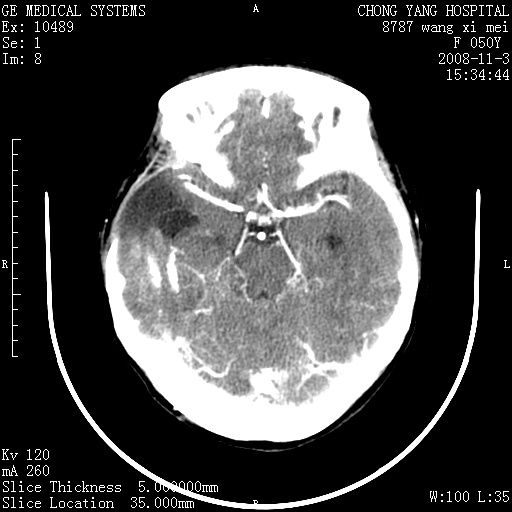

标题: CT16469:女,50岁,胶质瘤术后6年,今平扫加增强,请大家帮 [打印本页]

标题: CT16469:女,50岁,胶质瘤术后6年,今平扫加增强,请大家帮

右颞骨局限性缺如,局部脑组织无外隆。右颞叶可见片状脑脊液样低密度影,边缘较清,右侧侧脑室三角区可见一块状等密度影,且伴有强化,余未见明显异常改变。

考虑:右大脑术后改变伴肿瘤复发。

少突胶质细胞瘤.手术是不可能做净的.其发展较慢.复发是必然的。

考虑右侧颞顶叶胶质瘤术后复发。

应考虑肿瘤复发,右颞顶叶已出现轻度强化肿块.必要时可与原片比较以下.

右侧颞顶部混杂密度影,内有钙化,有占位效应。应该是复发灶。结合术后片更好。

胶质瘤是易复发的,这个病人有复发灶